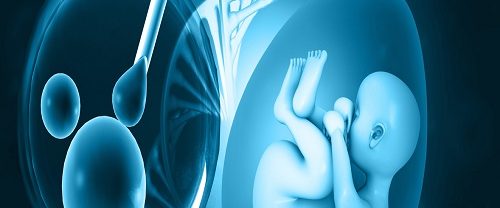

Tüp Bebek Tüp bebek, doğal yollarla gebe kalmakta zorluk yaşayan çiftlere yardımcı olmak amacıyla uygulanan bir tedavi yöntemidir. İşlem genellikle aşağıdaki adımları içerir: Yumurtalık Uyarımı: Tüp bebek tedavisinin ilk adımı, kadının yumurtalıklarının uyarılmasıdır. Bu, hormonal ilaçlar kullanılarak gerçekleştirilir. Hormon ilaçları, yumurtalıkların birden fazla yumurta üretmesini sağlar. Normalde kadın her ay bir tane yumurta üretirken, bu…

IVF İn Vitro Fertilizasyonun Temel İlkesi IVF İn Vitro Fertilizasyon, doğal olarak gebe kalamayan çiftlere yardımcı üreme teknikleri arasında en yaygın kullanılan yöntemlerden biridir. Temel ilkesi, gametlerin (yumurta ve sperm) laboratuvar ortamında bir araya getirilerek döllenmelerinin sağlanması ve oluşan embriyoların rahim içine transfer edilerek gebelik elde edilmesidir. İn vitro fertilizasyon süreci, bir dizi aşamadan oluşur:…

Embriyo Genetik Tanısı Nedir? Embriyo Genetik Tanısı, preimplantasyon döneminde embriyoların genetik yapılarının incelenmesi ve değerlendirilmesi işlemidir. Bu tanı yöntemi, genetik hastalıkların tespit edilmesi, tekrarlayan düşüklerin önlenmesi, ileri yaşan anne adaylarında genetik riskin azaltılması ve cinsiyet seçimi gibi amaçlarla uygulanır. Embriyo Genetik Tanısının birinci amacı, genetik hastalıkların tespit edilmesidir. Bazı çiftler, genetik hastalık taşıyıcısı olabilir ve…